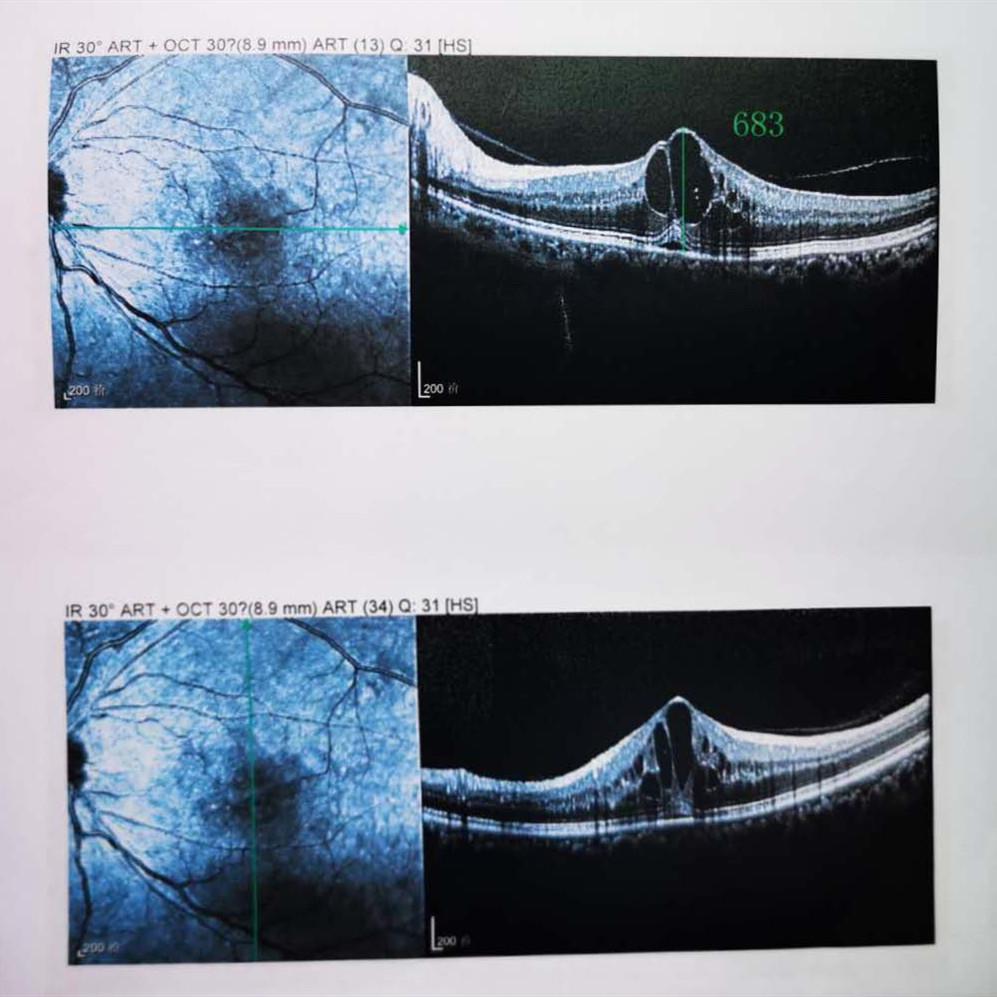

檢查結(jié)果顯示,武先生并沒有近視,右眼視力為1.0,但是左眼視力只有0.4,而且左眼視網(wǎng)膜各分支靜脈迂曲擴(kuò)張,全網(wǎng)膜面見火焰狀出血,黃斑區(qū)高度水腫、滲出,黃斑中心凹厚度約683um。

(武先生初次就診眼底OCT檢查圖)

而正常的矯正視力是1.0,黃斑中心凹厚度在200um左右。

“你這黃斑都腫到正常人的三四倍大了!”廈門眼科中心吳國基院長醫(yī)生告訴武先生,“你這是左眼視網(wǎng)膜中央靜脈阻塞伴黃斑水腫,你左眼的視力下降、看東西變形,是因?yàn)槟阕笱垡暰W(wǎng)膜的中央靜脈發(fā)生了阻塞、出血,導(dǎo)致眼底黃斑水腫了。”

那么,武先生的視力恢復(fù)情況如何呢?幸運(yùn)的是,經(jīng)過兩次玻璃體腔注藥術(shù),武先生左眼的黃斑水腫得到明顯改善,視力已經(jīng)恢復(fù)到0.8。

(武先生出院時(shí)眼底OCT檢查圖)